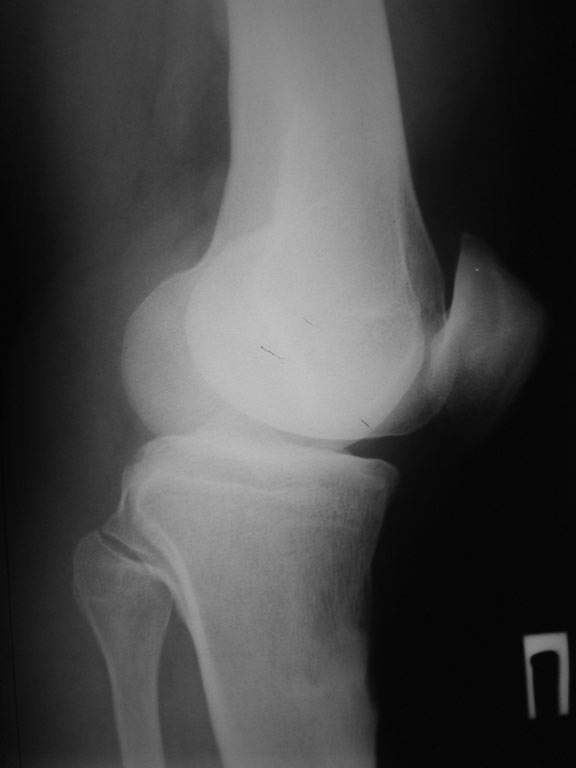

пациент наконец то объявился вновь и мы смогли выполнить новые снимки как лежа так и в нагрузке

если у вас остались силы, давайте обсудим